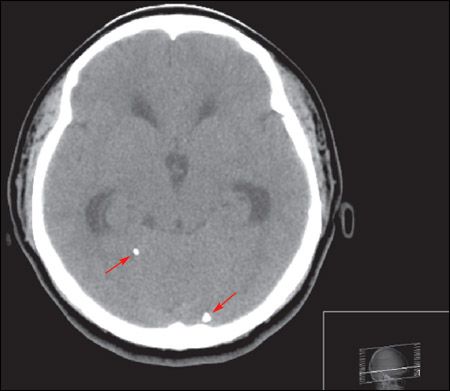

A cranial CT scan showed calcifications (arrows) scattered throughout the brain parenchyma with hydrocephalus. Intravenous ceftriaxone and metronidazole were started; phenytoin was added after seizures developed. Results from blood cultures were negative. The patient underwent a ventriculoperitoneal shunt. Results of cerebrospinal fluid analysis and culture, Cytomegalovirus serology, Toxoplasma serology, and tuberculosis polymerase chain reaction were all negative. Serology for Taenia solium was reactive. Postoperatively, albendazole (800 mg/d) and dexamethasone were started.

Neuroimaging may show a nonenhancing hypodense lesion, variable degrees of edema, calcifications, or hydrocephalus. Conditions that can present with similar features include toxoplasmosis, schistosomiasis, tuberculosis, cytomegalovirus infection, abscess, primary brain and metastatic cancers, trichinosis, and sarcoidosis. Finding a scolex as a mural nodule within the cyst is pathognomonic for neurocysticercosis. The appearance on CT or MRI scans is frequently nonspecific and may be difficult to differentiate from other brain lesions. A definitive diagnosis can be made using proposed diagnostic criteria based on clinical presentation, imaging, serology, and epidemiological data.3